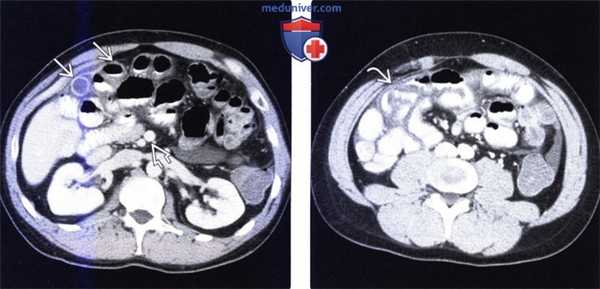

(Слева) На аксиальной КТ с контрастным усилением, выполненной мужчине 27 лет, у которого появилась боль и рвота, определяется, что тонкая кишка целиком, включая двенадцатиперстную кишку, располагается справа от средней линии. Слепая кишка расположена центрально, а ободочная кишка — справа от средней линии.

(Справа) На рентгенограмме, полученной при рентгеноскопии верхних отделов ЖКТ у этого же пациента, определяется частичная обструкция на уровне дистальных отделов двенадцатиперстной кишки, которая не пересекает среднюю линию, но имеет своеобразный вид, напоминающий букву Z или «штопор». На операции подтвердилась мальротация и обструкция двенадцатиперстной кишки, обусловленная тяжами (Ледда). (Слева) На аксиальной КТ, выполненной женщине 4 7 лет с жалобами на боль, определяется, что верхняя брыжеечная артерия и вена находятся в положении, обратном типичному, а тонкая кишка целиком расположена в брюшной полости с правой стороны. Определяется утолщение стенки тощей кишки и ограниченный асцит, а также расширение просвета кишки.

(Справа) На аксиальной КТ с контрастным усилением у этой же пациентки визуализируются другие сегменты тощей кишки с утолщенной стенкой. Мальротация подтвердилась на операции наряду с ишемическими изменениями тощей кишки, которая была пережата из-за спаек.

(Справа) На рентгенограмме, полученной при рентгеноскопии верхних отделов ЖКТ у этого же пациента, определяется частичная обструкция на уровне дистальных отделов двенадцатиперстной кишки, которая не пересекает среднюю линию, но имеет своеобразный вид, напоминающий букву Z или «штопор». На операции подтвердилась мальротация и обструкция двенадцатиперстной кишки, обусловленная тяжами (Ледда).

(Слева) На аксиальной КТ, выполненной женщине 4 7 лет с жалобами на боль, определяется, что верхняя брыжеечная артерия и вена находятся в положении, обратном типичному, а тонкая кишка целиком расположена в брюшной полости с правой стороны. Определяется утолщение стенки тощей кишки и ограниченный асцит, а также расширение просвета кишки.